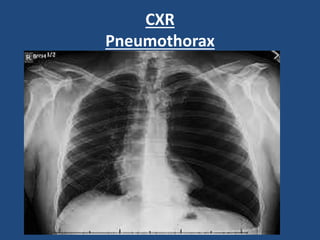

2-CXR:

(Wide mediastinum, pneumothorax)

Pneumothorax